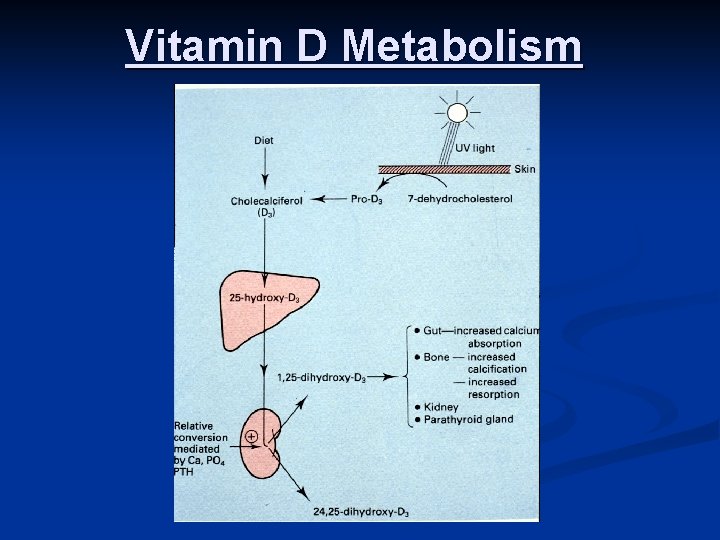

Biochemistry of Vitamin D 3 – Brief Review Vitamin D 3 (cholecalciferol) is synthesized in the skin, with UV light, from 7 -dehydrocholesterol n Vitamin D 3 is hydroxylated twice – first in the liver, to 25 hydroxycholecalciferol, then in the kidney, to 1, 25 dihydroxycholecalciferol, the most potent form of Vitamin D n

Vitamin D metabolism

Vitamin D Metabolism